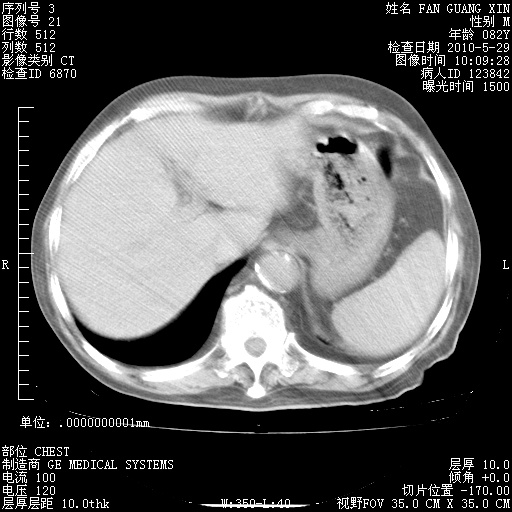

再治疗10天后的肺部CT

从白细胞总数和中性比例看好像合并感染。肺部纹理好像比上次多,支气管炎?其他感染?

阅读此次胸部CT,肺间质渗出性改变较入院时有吸收。目前从体温、白细胞、中性分叶明显增高,肯定存在细菌感染(发生医院感染哦,若无消化道及泌尿系统等感染的依据,肺部感染可能大)。若你院头孢哌酮舒巴坦钠耐药率较高,同意你的方案,若48小时体温仍高,可考虑使用碳青霉稀类抗菌药物,同时可予超声雾化、注意滴数时加大液体量。白蛋白33.30g/L较低哦,需加强营养等支持治疗。